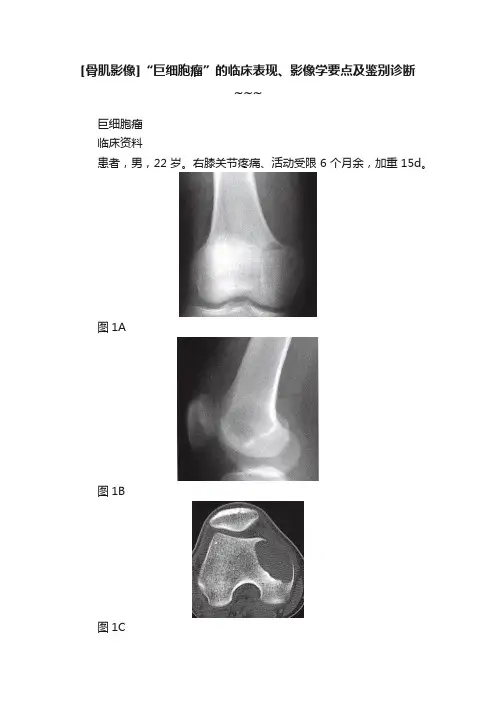

[骨肌影像]“巨细胞瘤”的临床表现、影像学要点及鉴别诊断~~~巨细胞瘤临床资料患者,男,22岁。

右膝关节疼痛、活动受限6个月余,加重15d。

图1A图1B图1C图1D图1E图1F影像学报告描述右股骨远端正、侧位(图1A、图1B),右股骨内髁偏心性骨质破坏,病灶达关节面下,皮质变薄,部分不清晰。

CT平扫(图1C)及冠状位重组(图1D),清晰显示偏心性骨质破坏,略膨胀,髓腔侧缘边界清楚,局限性硬化,外缘皮质部分消失。

MRI矢状位T1WI(图1E),病变呈均匀的略高于肌肉的低信号;冠状位梯度回波序列(图1F),病灶信号不均匀增高,内可见多发片状低信号影。

影像诊断与最后诊断均为:右股骨远端巨细胞瘤。